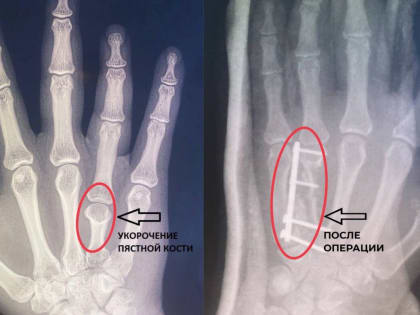

Владимирские врачи из областного центра спецмедпомощи сделали жизнь одной девушки проще, удлиннив ей безымянный палец на правой руке.

Врачи в Александрове удлинили пациентке палец Пациентка обратилась в больницу с жалобами на укорочение среднего пальца на правой руке, из-за чего он не мог полностью сгибаться и разгибаться.